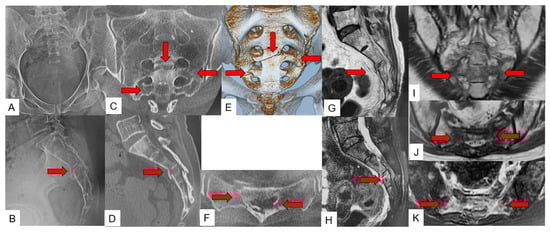

3.2. Accompanying Other Fracture

3.3. SIF Fracture Pattern

3.4. Typical SIF Case